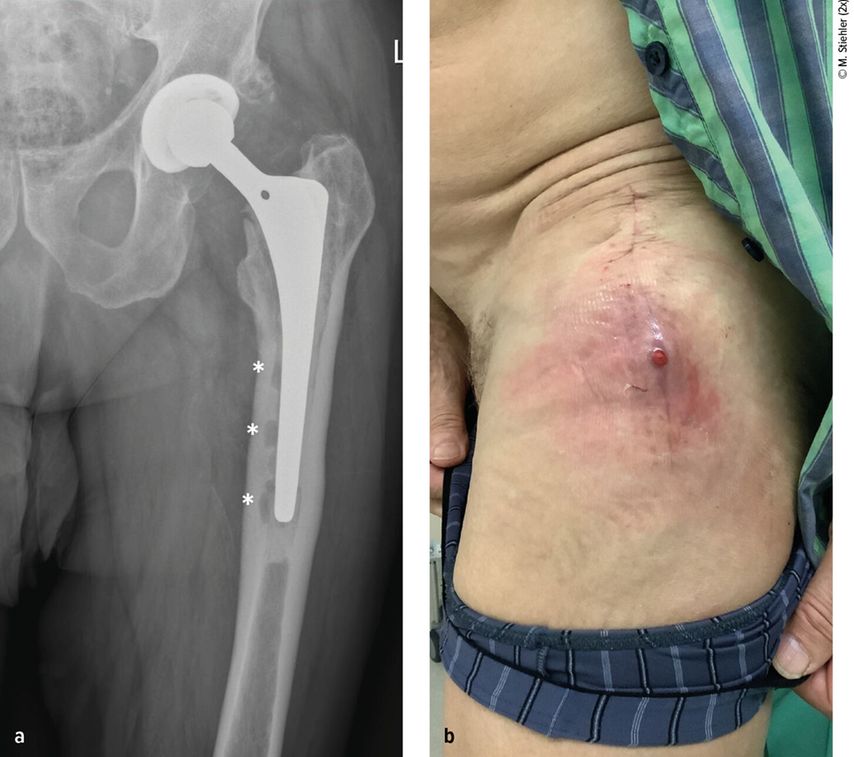

Abb. 1: Patient mit chronischer Hüftendoprotheseninfektion. Radiologisch zeigen sich infektionsbedingte periprothetische Osteolysen (*, a) und klinisch imponiert eine kutane Fistel (b).

Diagnostik der PPI

Anhand der klinischen Zeichen und der Symptomdauer unterscheidet man zwischen akuter und chronischer PPI. Die akute PPI ist durch eine kurze Symptomdauer (<3 Wochen) charakterisiert. Sie tritt entweder in der frühen (<4 Wochen) Phase nach endoprothetischem Gelenkersatz (akute postoperative PPI) oder aber verzögert (>4 Wochen, ggf. erst mehrere Jahre) nach Endoprothesenimplantation im Rahmen einer hämatogenen Streuung eines endoprothesenfernen Infektionsherdes (akute hämatogene PPI) auf. Typischerweise imponieren hier lokale Infektionszeichen wie Schmerzen, Schwellung, Rötung, Überwärmung oder eine prolongierte Wundsekretion (>7 Tage). Die Unterscheidung zwischen akuter und chronischer PPI basiert auf den Eigenschaften des bakteriellen Biofilms. Beim Vorliegen einer akuten PPI ist von einem unreifen bakteriellen Biofilm auf der Endoprothesenoberfläche auszugehen. Bei der chronischen PPI (>4 Wochen postoperativ) mit längerer Symptomdauer (>3 Wochen) liegt hingegen ein potenziell reifer Biofilm vor. Die klinischen Symptome sind in der Regel weniger ausgeprägt. Jedoch kann das Vorliegen einer kutanen Fistel oder von radiologischen Zeichen der Endoprothesenlockerung auf eine chronische Infektion hinweisen (z. B. Abb. 1).